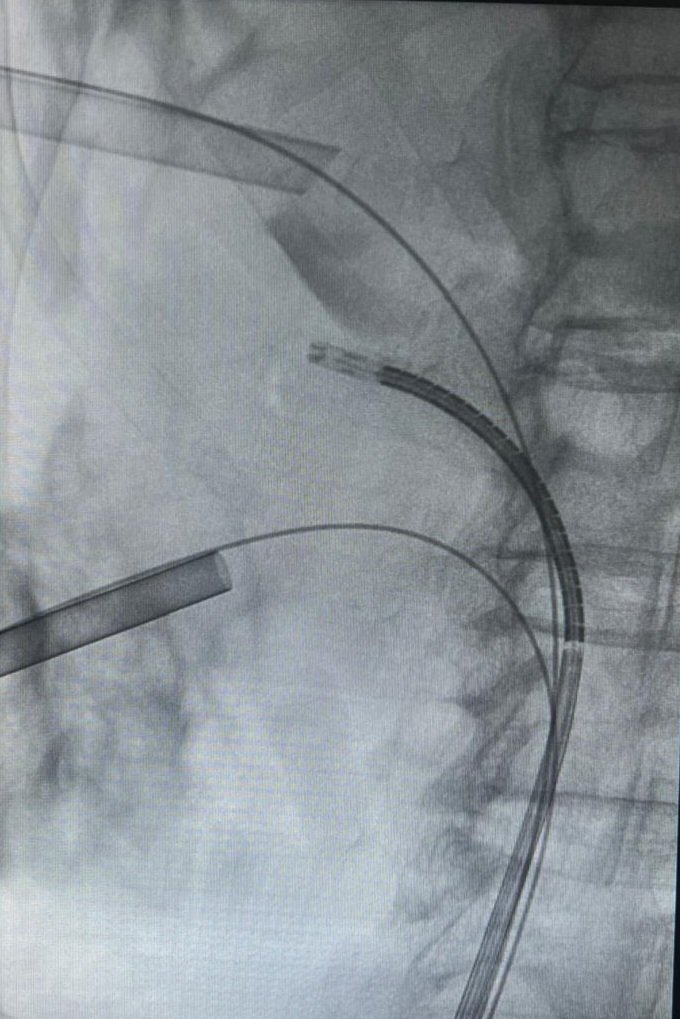

Continuamos con cirugía percutánea para el tratamiento de la litiasis renal con el Dr.Marcos Cepeda Delgado.

Advanced supine #PCNL workshop at #HURH with @CoralManso US & fluoroscopy Complex cases #miniECIRS

#uppercalyx Thanks to @bsc_urology for the support #lithovueElite Proud of my team! @kikegonzalez11 @PaulaMaple

3

7

22

#uppercalyx Thanks to @bsc_urology for the support Proud of my team! @kikegonzalez11 @MariaJoseLnza

2

5

23

Honored to be part of the live surgery session at #EAU25

#MiniECIRS with @CoralManso & @duque_dra in elderly patient Semi-live #Miniperc to the upper calyx in #supine Grateful to @ROC_Urologia for the hospitality, we felt at home, and @AlbertoBreda1 @Uroweb for the invitation

8

44